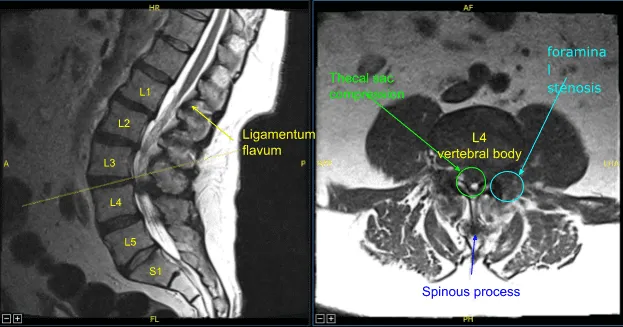

The patient presented to our clinic with signs and symptoms of lumbar stenosis. Having failed nonsurgical treatment, surgery was recommended to decompress the lumbar spine. The risks, benefits, alternatives, and potential complications of the surgery were explained to him.

Ligamentum flavum was exposed and was noted to be significantly hypertrophied. Extensive arthritic changes and osteophytes were noted in this part of the spine. Kerrison rongeurs were used to resect the ligamentum flavum exposing the dura.

Decompression was continued laterally until the thecal sac was fully decompressed. While decompressing the lateral recess with Kerrison rongeurs and exploring the lateral recess with Penfield instruments, a very small amount of clear fluid was seen. It was not determined if this was secondary to synovial cyst seen on preoperative MRI or a cerebrospinal fluid leak.